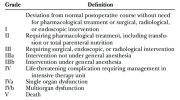

| 11:27, 13 במרץ 2024 | CLAVIEN - Dindo CLASSIFICATION.png (קובץ) |  |

168 קילו־בייטים | Roeitul | 1 | |